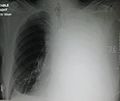

A large left sided pleural effusion as seen on an upright chest X-ray

A pleural effusion is usually diagnosed on the basis of medical history and physical exam, and confirmed by a chest X-ray. Once accumulated fluid is more than 300 mL, there are usually detectable clinical signs, such as decreased movement of the chest on the affected side, dullness to percussion over the fluid, diminished breath sounds on the affected side, decreased vocal resonance and fremitus (though this is an inconsistent and unreliable sign), and pleural friction rub. Above the effusion, where the lung is compressed, there may be bronchial breathing sounds and egophony. A large effusion there may cause tracheal deviation away from the effusion. A systematic review (2009) published as part of the Rational Clinical Examination Series in the Journal of the American Medical Association showed that dullness to conventional percussion was most accurate for diagnosing pleural effusion (summary positive likelihood ratio, 8.7; 95% confidence interval, 2.2–33.8), while the absence of reduced tactile vocal fremitus made pleural effusion less likely (negative likelihood ratio, 0.21; 95% confidence interval, 0.12–0.37).[6]

Imaging

A pleural effusion appears as an area of whiteness on a standard posteroanterior chest X-ray.[7] Normally, the space between the visceral pleura and the parietal pleura cannot be seen. A pleural effusion infiltrates the space between these layers. Because the pleural effusion has a density similar to water, it can be seen on radiographs. Since the effusion has greater density than the rest of the lung, it gravitates towards the lower portions of the pleural cavity. The pleural effusion behaves according to basic fluid dynamics, conforming to the shape of pleural space, which is determined by the lung and chest wall. If the pleural space contains both air and fluid, then an air-fluid level that is horizontal will be present, instead of conforming to the lung space.[8] Chest radiographs in the lateral decubitus position (with the patient lying on the side of the pleural effusion) are more sensitive and can detect as little as 50 mL of fluid. At least 300 mL of fluid must be present before upright chest X-rays can detect a pleural effusion (e.g., blunted costophrenic angles).